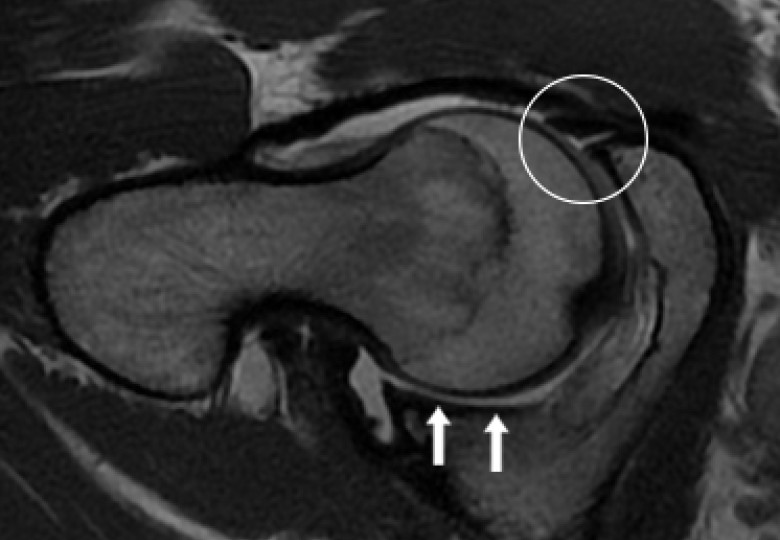

• Labral hyperplasia ( enlargement of the cartilage at the margin of the hip socket) was a predictor of microinstability.

• Increased acetabular anteversion (a measure of the angle of the hip socket) and decreased lateral centre edge angle (LCEA, a measure of hip socket coverage) were associated with microinstability.

• The absence of osteophytes (bone spurs) and the absence of a positive ischial spine sign (a specific feature seen on X-rays) were also associated with microinstability.